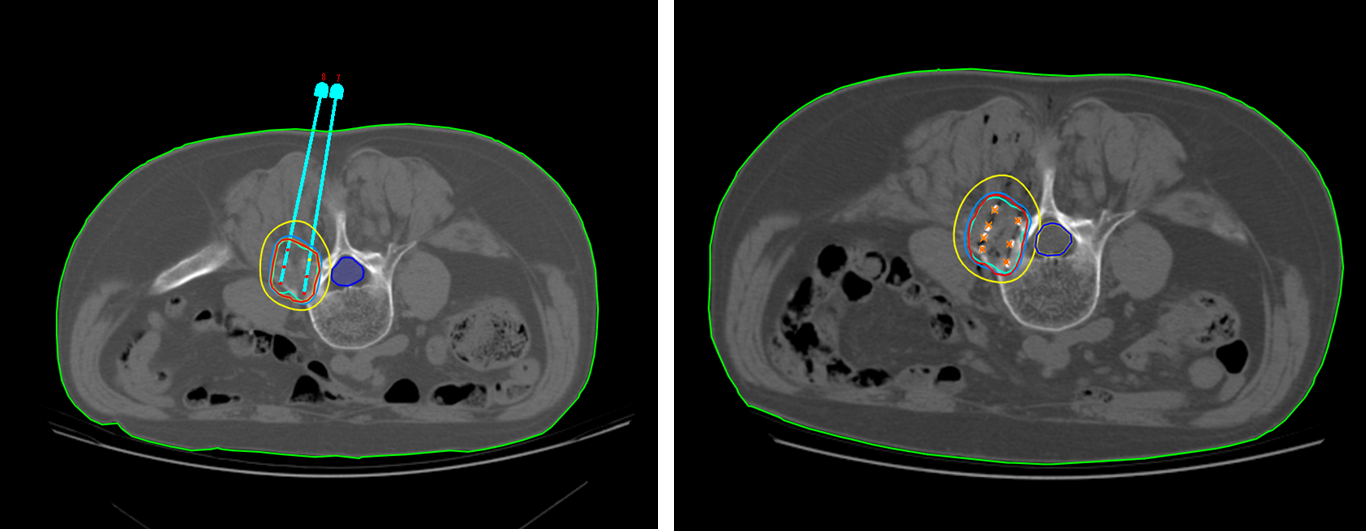

术前TPS计划

手术在CT引导下完成,术中应用由北京启麟科技公司提供的3D模板定位,进针入径为8个针道,准确将穿刺针依次植入肿瘤病灶内,根据TPS计划向病灶内植入30枚125I放射性粒子,整个术程顺利,无脊髓损伤等不良反应发生,术后1周患者疼痛症状逐渐缓解,疼痛评分降至3分。

术中应用3D模板精准定位及术后验证

术前、术后TPS计划对比完全吻合